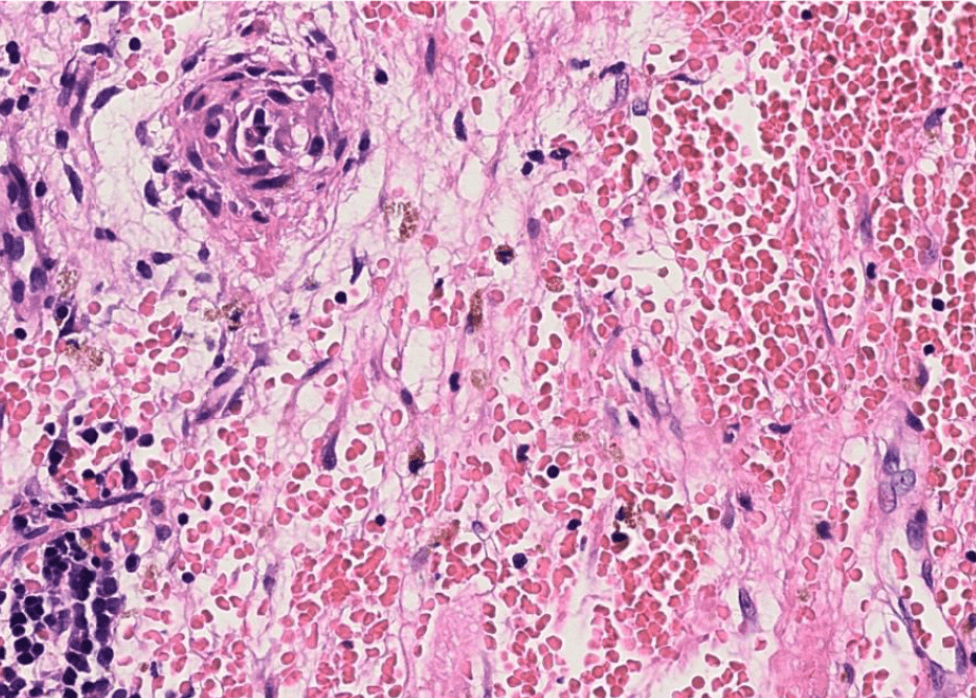

Organ: Lymph node

Diagnosis: Lymphoid hyperplasia

Descriptions:

- Increased number and size of follicles

- Follicles have distinct mantle zones and polarized germinal center

- Normal cell composition and tingible-body macrophages in the follicles